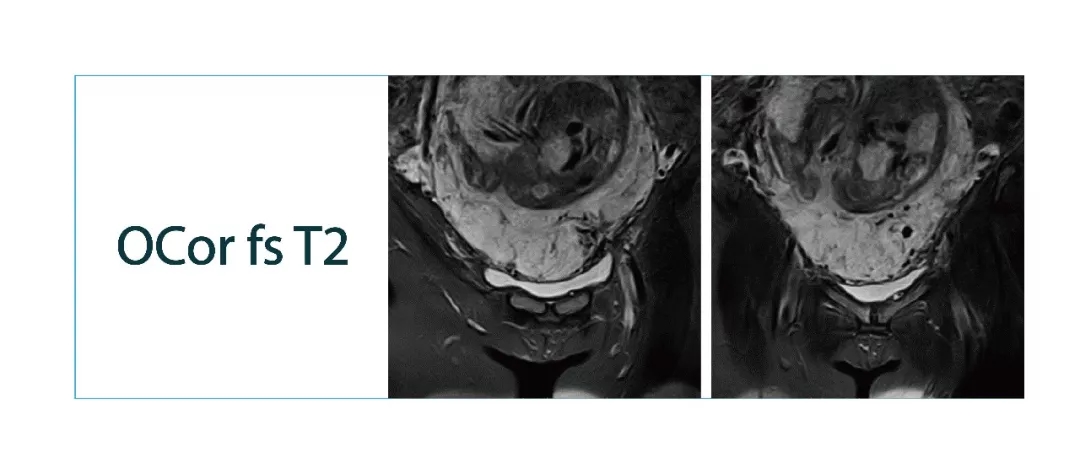

【朗润影像档案】磁共振影像病例分享(编号20180302)